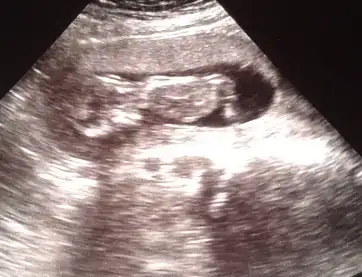

dr soylemeden siz gorun genital nub teorisi ( bebegin cinsiyeti)

$11+1.webp $12+3(2).webp $12+3.webp $13+2.webp

Resimlere tıkladığınızda haftaları yazıyo:emir_bebek::emir_bebek:

Arkadaşlar ablamında benimde bebeğin cinsiyeti sanırım netleşti.

bizim dr kesin erkek dedi ablamın dr da erkek gibi kıza pek heveslenme demiş=(